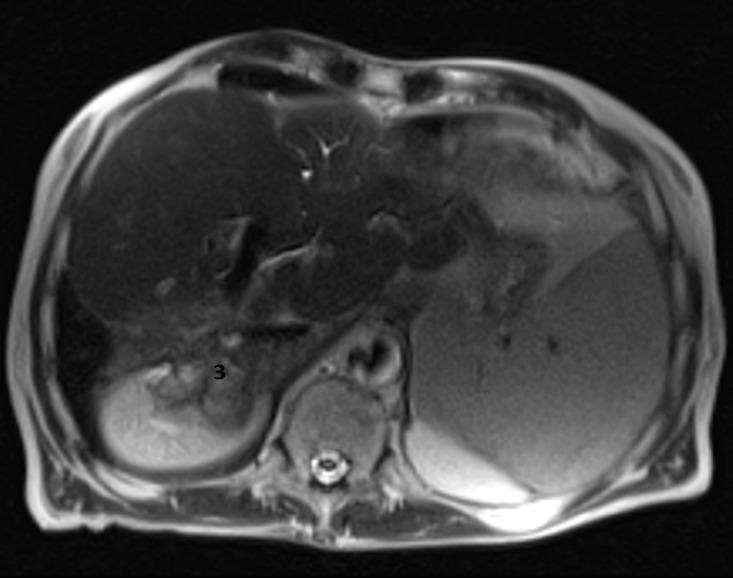

A 70-year-old man presented to the emergency department with diminished consciousness and disorientation, and was diagnosed with hepatic encephalopathy. The patient was diagnosed in 1993 with a metastatic small bowel NET, for which he twice underwent hepatic surgery, with metastatic resection in 1993 and a right hepatectomy in 2002 to remove two hepatic metastases. In 2003, the patient started first-line chemotherapy and in 2004 started the first of three consecutive biological treatments, followed by radio-molecular therapy, achieving stable disease for 14 years. Disease progression was identified and he underwent an endoscopic retrograde cholangiopancreatography. However, in 2019 advanced liver disease was identified. We diagnosed the development of acquired hepatocerebral degeneration, an unusual long-term side effect after multiple hepatic procedures.

一名70岁男性因意识减退和定向障碍就诊于急诊科,被诊断为肝性脑病。该患者于1993年被诊断为转移性小肠NET,为此他接受了两次肝脏手术,1993年进行了转移性切除术,2002年进行了右肝切除术以切除两处肝转移灶。2003年,患者开始一线化疗,2004年开始连续三次生物治疗中的第一次,随后进行放射分子治疗,病情稳定了14年。发现疾病进展后,他接受了内镜逆行胰胆管造影术。然而,2019年发现了晚期肝病。我们诊断为获得性肝脑变性的发生,这是多次肝脏手术后一种不常见的长期副作用。